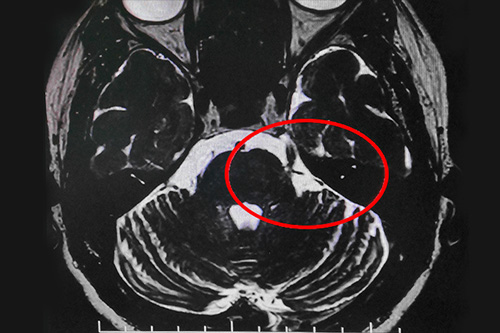

在辦理入院手續(xù)后,醫(yī)生詳細(xì)了解了王大媽的病史資料,并為其做了三叉神經(jīng)MRTA平掃+增強(qiáng)等相關(guān)檢查。結(jié)合影像資料,沈建康教授判定王大媽的三叉神經(jīng)痛系血管壓迫所致,且手術(shù)指征明顯,未見(jiàn)明顯手術(shù)禁忌癥。

▲患者三叉神經(jīng)受壓迫區(qū)域